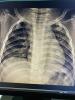

Нам сделали укол дексы, педиатр там сразу сказала, что пневмонии нет но я напросилась сделать рентген.

Его сделали за пару минут и он уже готов, и тоже бесплатно 🥹

@maybemaybe, усиление легочного рисунка а так никаких уплотнений